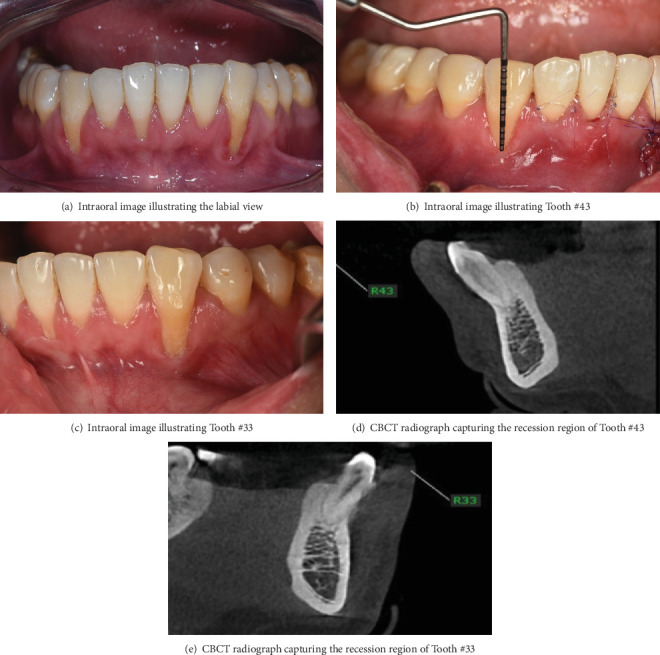

背景:目前已经提出了几种治疗牙龈萎缩的方法,并取得了积极的效果和临床可接受的结果。然而,大多数需要两阶段的手术,有一些缺点。本临床报告描述了改良的旋转皮瓣技术结合双成分释放切口和单侧隧道入路治疗牙龈退缩的治疗过程和临床结果。方法:32岁男性,非吸烟者,经正畸治疗后,33牙后退6mm, 43牙后退8mm。从硬腭取8 × 12 × 1.5 mm大小的结缔组织移植物。采用裂厚法在犬的内侧建立隧道皮瓣。在第二前磨牙的远端放置一个缩小的切口,包括一个弯曲的部分,遵循犬齿和前磨牙的颈椎轮廓,并以双部分释放切口结束。将移植物插入隧道,将牙龈瓣重新定位并固定以覆盖暴露的牙面。结果:随访6个月和1年,平均根管覆盖率100%,无疼痛和牙敏。结论:虽然需要进一步的研究和长期随访来评估该手术的有效性,但本病例报告表明,该技术不仅增加了根覆盖,而且仅在一次手术预约中就使粘膜宽度角化。

Background: Several techniques have been proposed to deal with gingival recession and gain positive effectiveness and clinically acceptable results. Nevertheless, most require a two-stage surgical procedure with several drawbacks. The present clinical report describes the treatment procedure and clinical outcomes of a modified rotated flap technique incorporating a double-component releasing incision and one-sided tunnel approach for the management of gingival recession. Methods: A 32-year-old male nonsmoker presented with a recession of 6 mm at tooth 33 and 8 mm at tooth 43 after orthodontic treatment. An 8 × 12 × 1.5-mm-size connective tissue graft was harvested from the hard palate. A tunnel flap was created on the mesial side of the canine using split-thickness technique. A reduced incision was placed distal to the second premolar, consisting of a curved segment that followed the cervical contours of the canine and premolars, and concluded with a double-portion releasing incision. The graft was inserted into the tunnel, and the gingival flap was repositioned and secured to cover the exposed tooth surface. Results: After the 6-month and 1-year follow-ups, the mean root coverage rate was 100% without pain and tooth sensitivity. Conclusions: Although additional studies and long-term follow-up will be needed to evaluate the effectiveness of this procedure, this case report showed that this technique not only increases root coverage but also keratinized the mucosa width in only one surgical appointment.